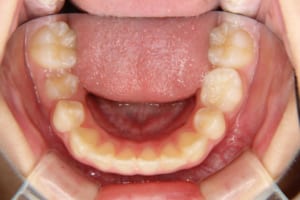

治療前

| 年齢・性別 | 11才 女性 |

| 主訴 | 八重歯の生え方が気になる |

| 使用した装置 | 子どもの矯正治療(前期治療) 緩徐拡大装置 マルチブラケット装置 大人の矯正治療(後期治療/成人矯正治療) マルチブラケット装置 デーモンブラケット シルバーワイヤー 歯科矯正用アンカースクリュー(2本) ホールディングアーチ トランスパラタルアーチ |

| 抜歯および非抜歯 | 上顎:両側第一小臼歯 下顎:右側第二小臼歯 先天欠如:下顎左側第二小臼歯 乳歯:下顎左側第二乳臼歯 |

| その他/備考 | 上の犬歯が生えるためのスペースが全くない状態でした。放置すると重度の八重歯になることが想定されるケースです。 今回はあごの成長も利用しながら治療をするために、早めに後期治療(大人の矯正治療)に移行しました。 治療後レントゲン写真を見たところ、上顎前歯に若干の歯根吸収を認めました。 |